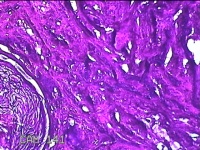

下颌部包块

性别

男

年龄

47岁

临床诊断

皮脂腺囊肿

一般病史

发现下颌部包块3年余,无疼痛及不适。

标本名称

大体所见

灰白暗红色带皮肤结节1.5x1.3x0.8cm一个,表面糜烂,切开结节呈实性,切面灰白粉红色,质软。